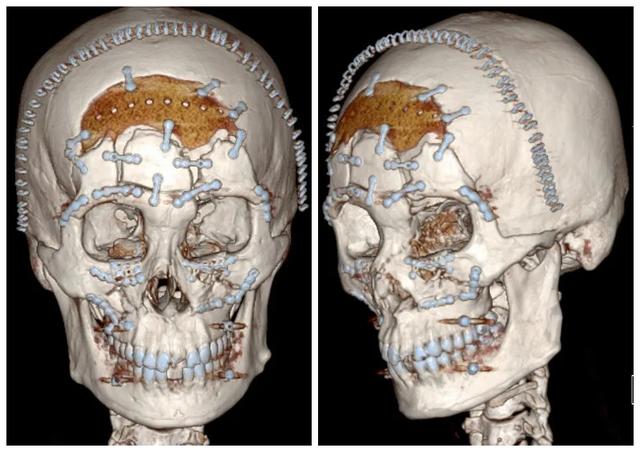

由CT可以看出,腦內(nèi)有血腫,中線有移位,證明有腦疝。而在顱骨三維重建圖中顯示,顱骨有粉碎性骨折,不僅有游離的碎骨片,在顱面交界區(qū)域,其左右兩側(cè)眶額部,鼻根上方的額眶上中部都有骨折移位,同時(shí)他的眶下壁和上頜骨也有骨折。

硬膜修補(bǔ)完畢后,使用PEEK連接片將左右眶額、額眶上中三個(gè)主要帶血運(yùn)的骨折塊連接起來,為二期顱骨修補(bǔ)手術(shù)奠定基礎(chǔ)。

在術(shù)中,首先拆除了首次手術(shù)連接骨塊用的PEEK連接片,先固定移位不明顯的右眶額、額顳,再復(fù)位移位的左眶額,進(jìn)行固定,最后整復(fù)、拼接三塊骨塊。

最終,使用了20個(gè)連接片,和PEEK材料顱骨修補(bǔ)補(bǔ)片,將顱面各骨塊固定。